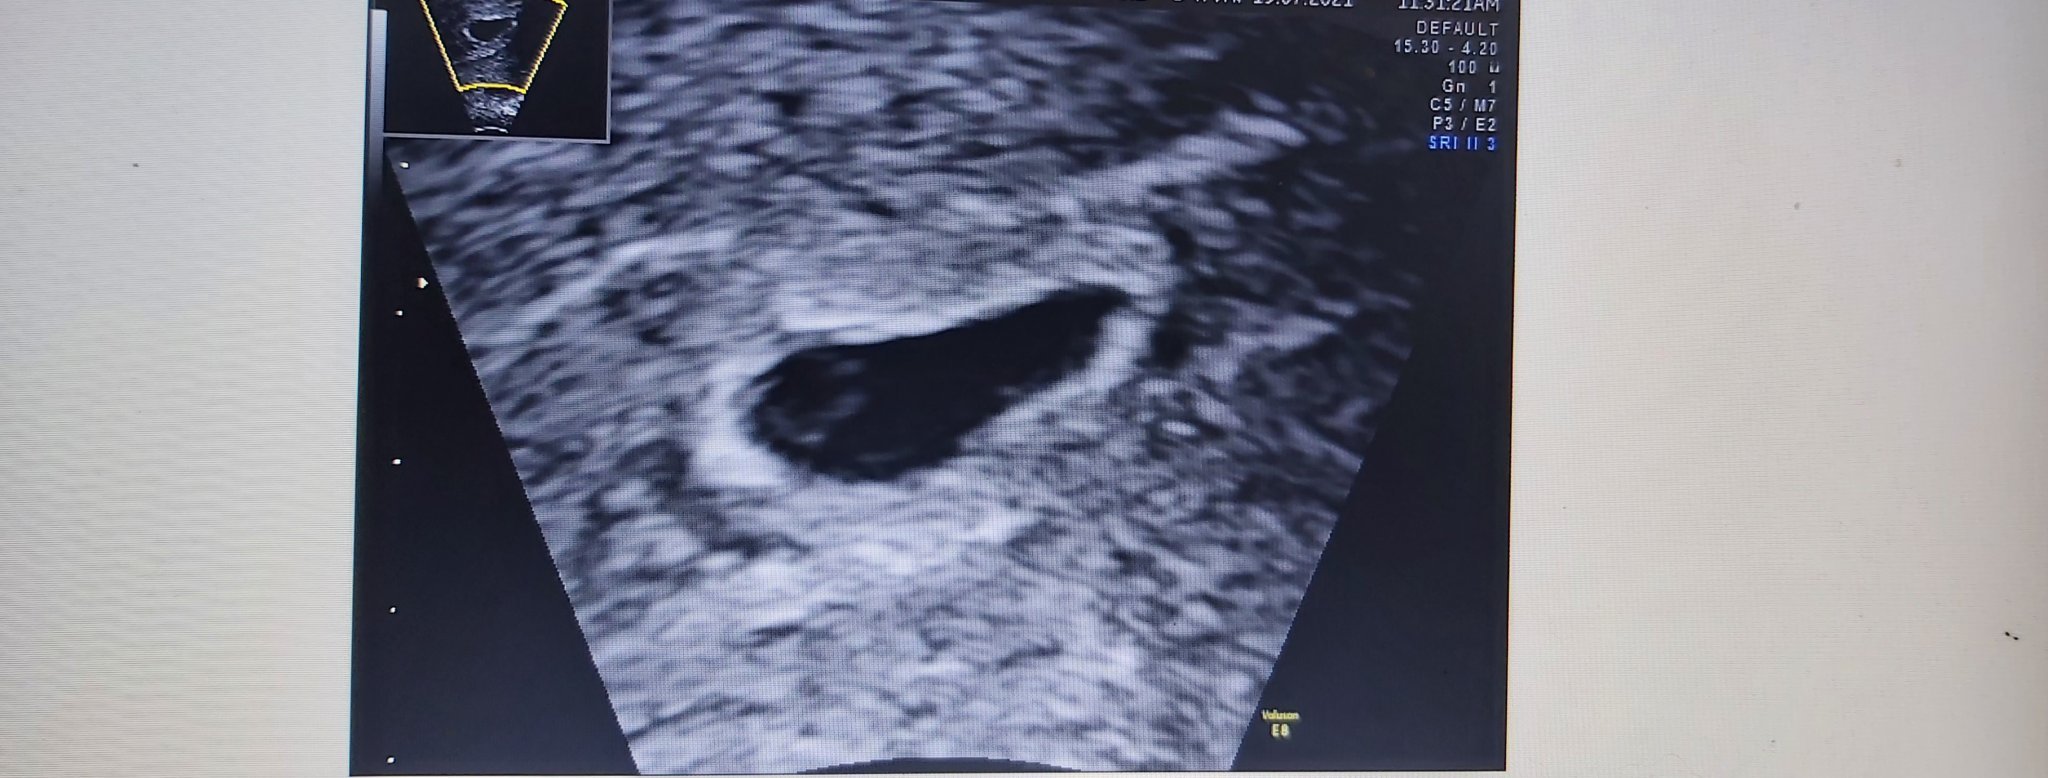

Моля, за мнение момичета! Това са снимките в 5 г.с. и 4 дни. Според вас размерите наред ли са? Сакче - 1,27см и ж.м.- 0,34 см. Предстои ми преглед да видим и чуем ембрион и сърдечна дейност и все си мисля дали се развива дали всичко е наред?🤔